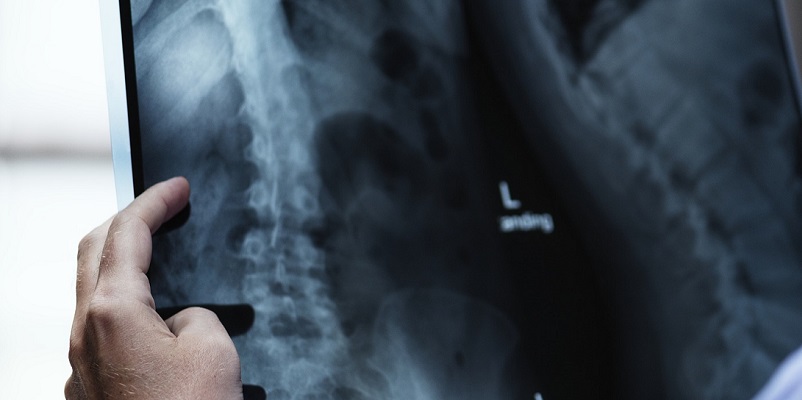

Obiettivo: ossa forti

Secondo questo studio, la vitamina E potrebbe essere fondamentale per la salute delle ossa

Dai risultati emersi, i ricercatori hanno concluso che il TRF ha il potenziale per prevenire il deterioramento osseo.

La vitamina E, quindi, non è solo fondamentale per la prevenzione della demenza, ma anche per lo sviluppo e la conservazione del nostro sistema scheletrico.